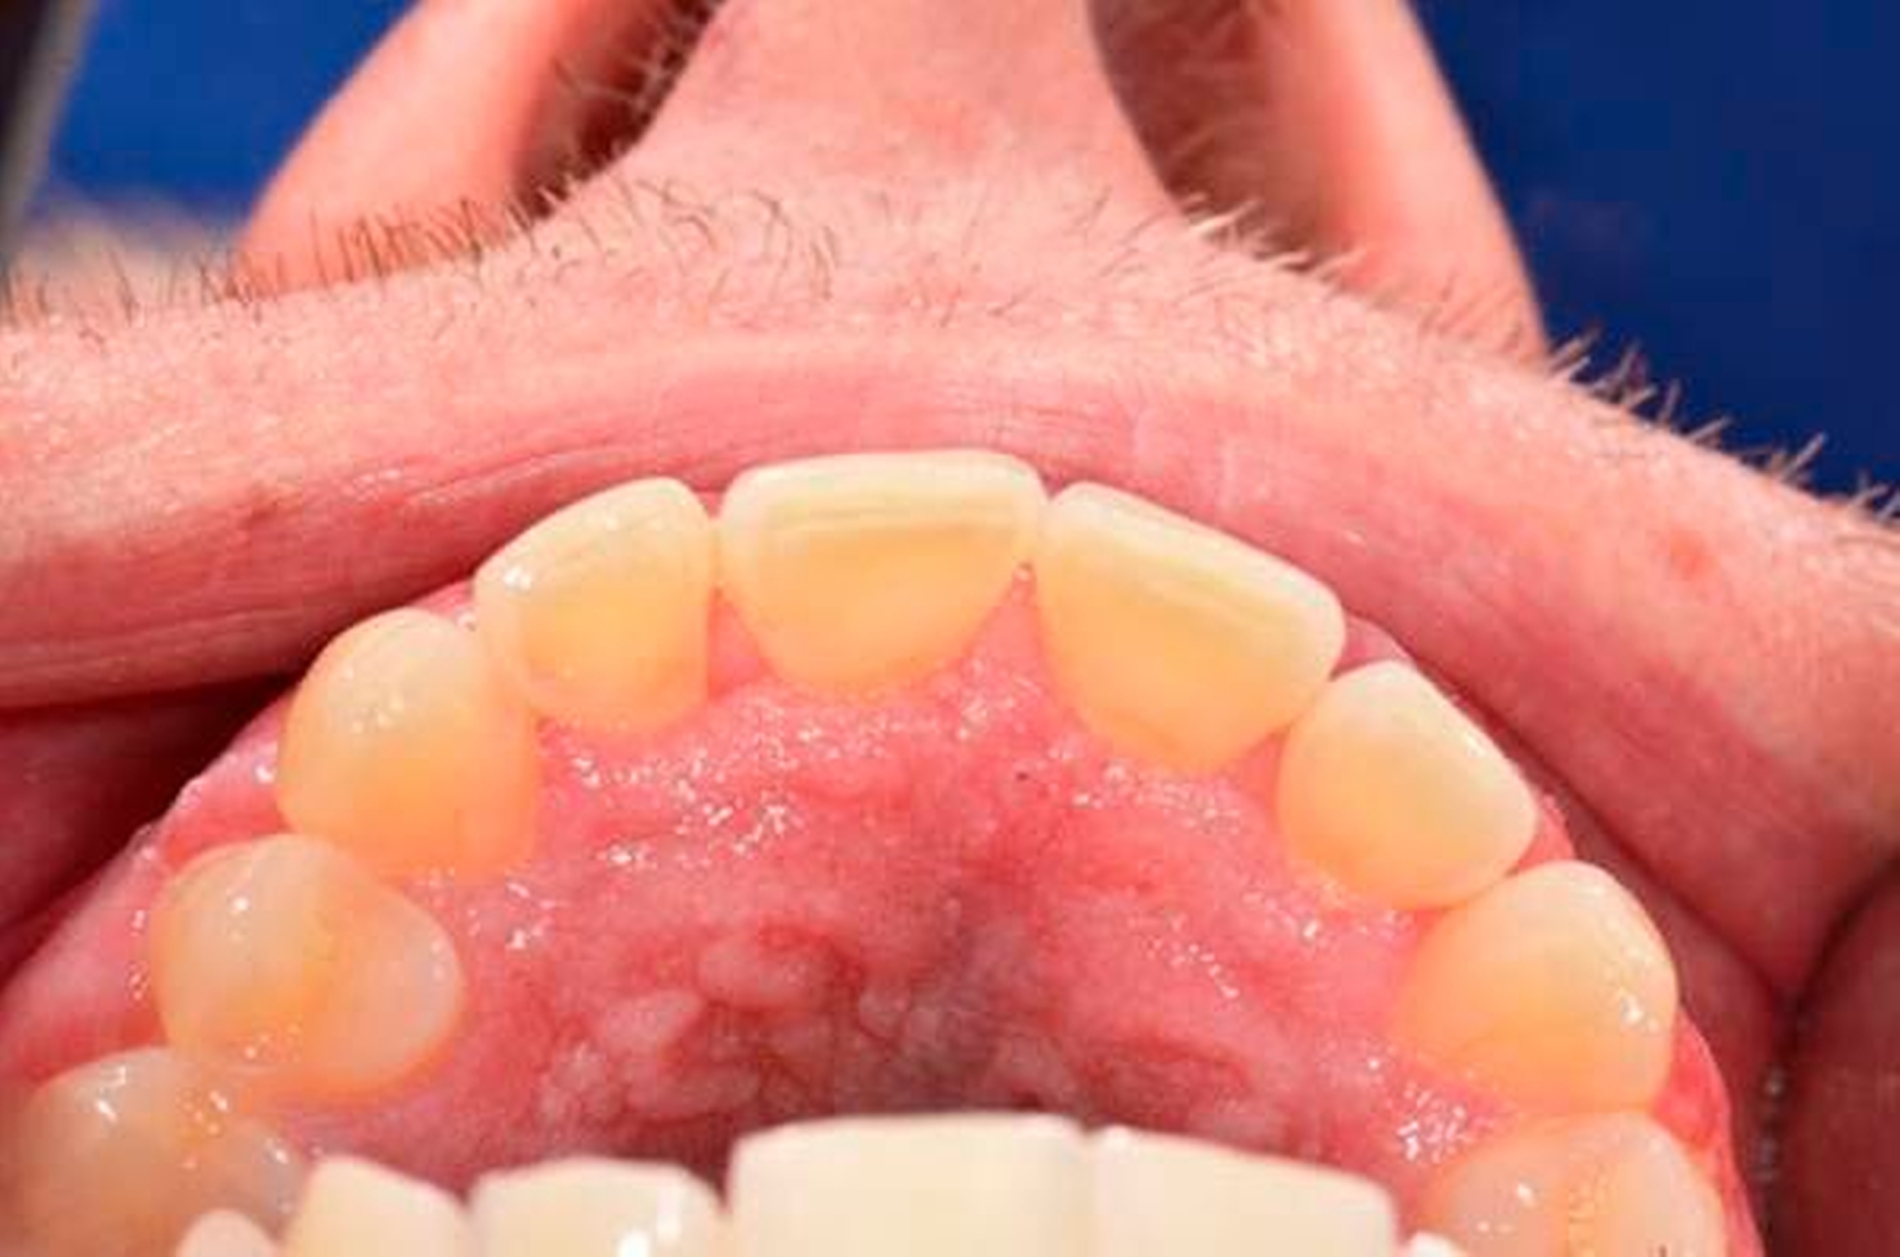

Neben der beschriebenen Läsion fanden sich oral leicht hyperplastische, papulöse Veränderungen der Gingiva vestibulär und palatinal ohne Hinweise auf Ulzerationen (Abbildungen 1 und 2). Vom klinischen Aspekt war der Befund daher gut vereinbar mit oralen Veränderungen infolge eines Morbus Crohn. Weiterhin gab der Patient eine Rötung an der Glans penis an. Der letzte Versuch einer MRT-basierten Dünndarmuntersuchung sowie einer Koloskopie und Gastroskopie scheiterte 2016 an der Compliance des Patienten.

Zur Diagnosesicherung bei der oralen Läsion empfahlen wir eine Probeentnahme der Mundschleimhaut sowie weiterführende serologische Untersuchungen. Die Stanzbiopsien des Gaumens und der vestibulären Gingiva erbrachten den histologischen Nachweis von oberflächlich perivaskulär gelegenen, kräftig lymphozytären, granulomatösen Infiltraten und passten somit zu einer mukokutanen Manifestation des bekannten Morbus Crohn. Serologisch ließen sich bis auf eine Vitamin-B12-Negativbalance, die in der Folge substituiert wurde, keine Auffälligkeiten nachweisen, insbesondere keine Autoantikörper.